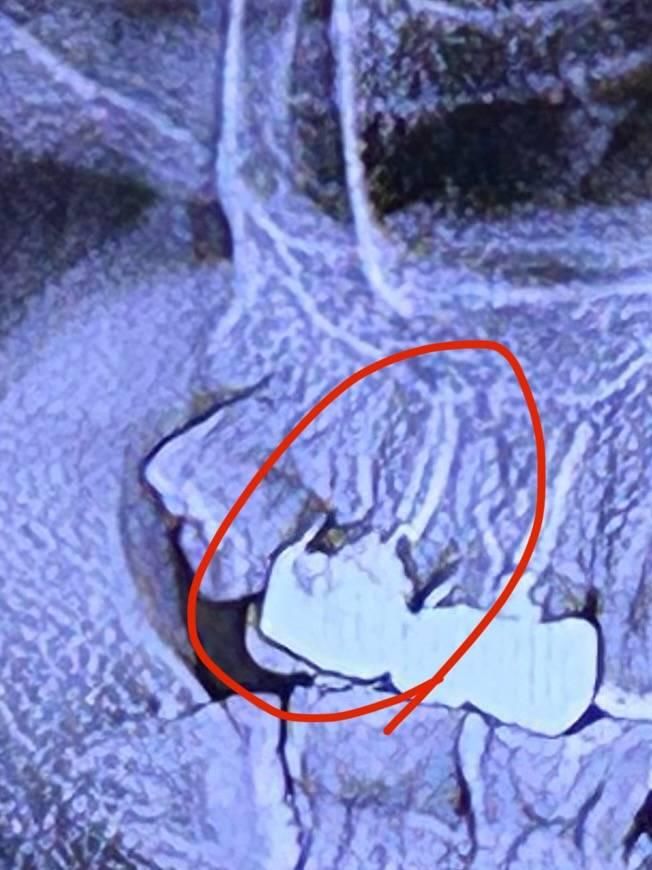

크라운과 치아 사이 공간이 충치로 보일 수 있나요?

해당 사진의 치아가 반년 전에 신경치료한 부위입니다.

그 옆 사랑니 발치를 하려고 다른 병원에 내원하니까 그 병원에서는 앞에 있는 신경치료 한 치아의 충치 정도가 심해보이는게 신경치료 후 오래된 치아라 사랑니 발치를 할 경우 어금니가 깨진다는 이유로 거절 했구요... (실제로는 반년밖에 안됐습니다...)

다시 신경치료 한 병원에 가서 물어보니까 신경치료는 문제 없이 마무리 했고, 해당 사진에서 검게 보이는 부분은 충치가 아니라 크라운을씌운 부분과 치아의 각도상 그렇게 보이는 거라고 하시는데 이게 가능한 이야기 인가요..?

다른 병원에서 크라운을 열어봐야 할지...실제로 저런 이유로 충치처럼 보일 수도 있는건가요?

사진상으로 보면 크라운 안쪽으로 충치가 많이 진행된 상태 같습니다. 신경치료는 문제가 없지만, 크라운 안쪽에처 2차 충치가 진행된거 같습니다.

사진으로 봤을 경우 크라운 경계 부위로 큰 충치가 보입니다. 사랑니를 발췌하는 도중에 해당 부위가 파절될 수 있습니다. 충치가 깊어 충치가 치조골 아래까지 진행이 되어 있다면 발치를 해야 할 수도 있습니다.

자세한 확인을 위해서 치과에서 진료를 받아보는 것을 권유드립니다.

다시 신경치료 한 병원에 가서 물어보니까 신경치료는 문제 없이 마무리 했고, 해당 사진에서 검게 보이는 부분은 충치가 아니라 크라운을씌운 부분과 치아의 각도상 그렇게 보이는 거라고 하시는데 이게 가능한 이야기 인가요..? -> 여러각도에서 치근단 사진을 찍어봐야 왜곡이 없이 확인될 것 같습니다